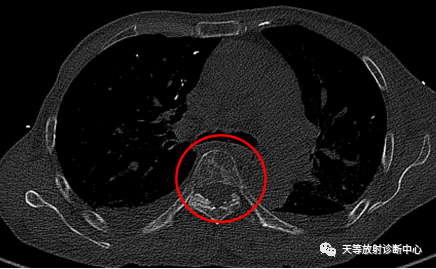

▲胸椎多发椎体溶骨性骨质破坏,穿凿或穿透性骨质缺损区。